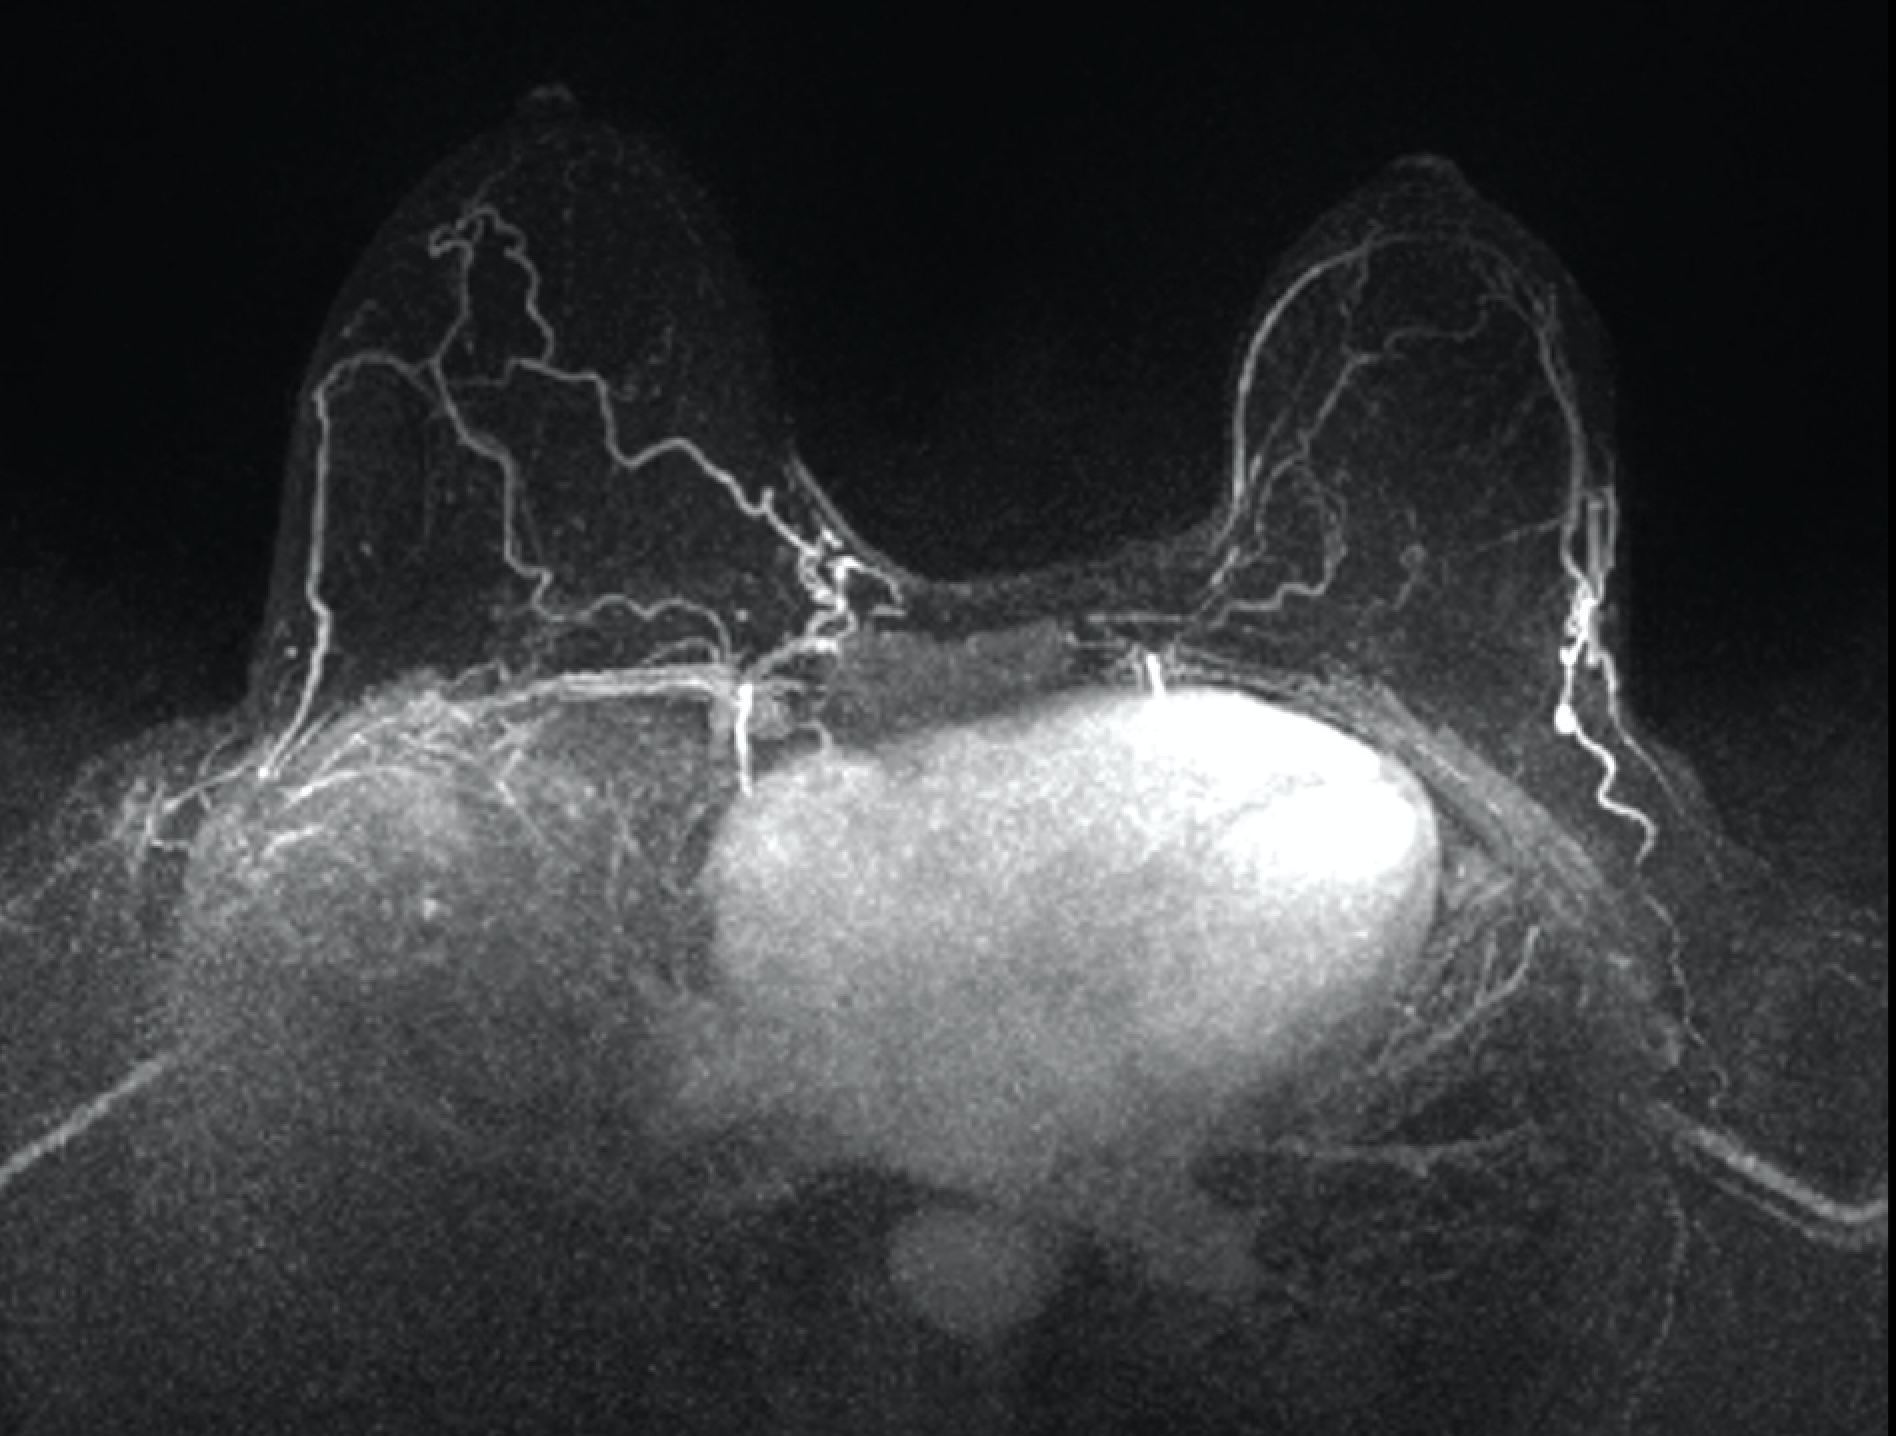

Figure 1

In observational studies, adding contrast-enhanced MRI to annual mammography in BRCA mutation carriers significantly improved detection of early, treatable breast cancers with a combined sensitivity of 94% compared to 39% with mammography alone.18,22,23 MRI provides a functional assessment of breast tissue. Contrast- enhanced MRI can detect microvascular changes and peritumoral inflammation as the contrast accumulates rapidly, and is then washed out rapidly, in more vascular tumors compared to benign breast tissue. Consequently, annual contrast-based MRI has been incorporated into breast cancer surveillance guidelines for women at the highest risk of breast cancer.24